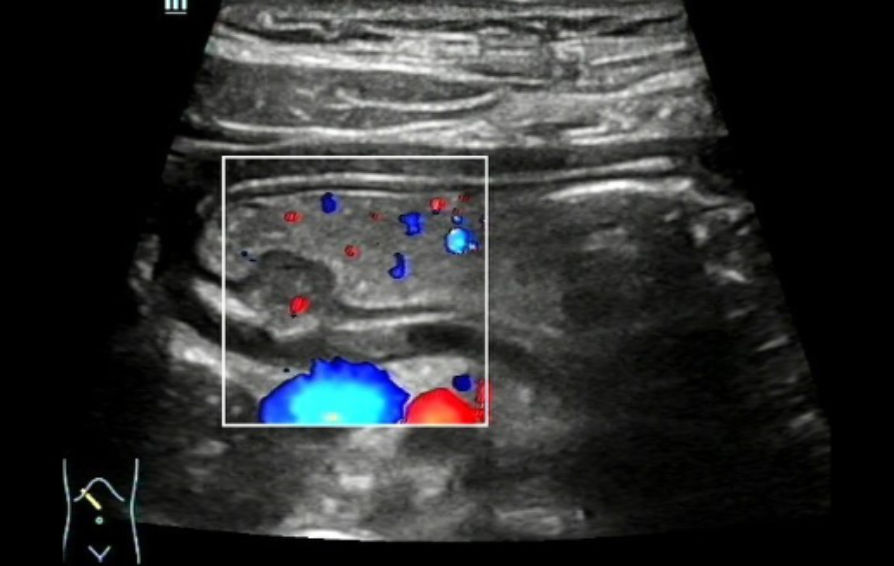

??? ???(instant gastrointestinal ultrasound aid) 500mL? ?? ???? ?? ? ??? ??? ?????. Gastric wall? ??? ???? ?? ??? ???? ?? ??????, Gastric antrum? lesser curvature? submucosal layer??? ? 1.36cm├Ś0.87cm ??? ?? ??? hypoechoic mass? ???????. ??mass? ????? ????? ????, ???? ?? ???? ???????.

???, mass? ??? ???? ?? ??? ?????, mass ????? ???? echogenicity ? ???????.(?? 3).

CDFI(Color Doppler Flow Imaging)? ?? ?? ??? ???? ??? mass? ??? ???? ??? ? ??? ???????. (?? 4) ??? ???? ?(stomach)? submucosal ??? ?????, ectopic pancreas? ???????.